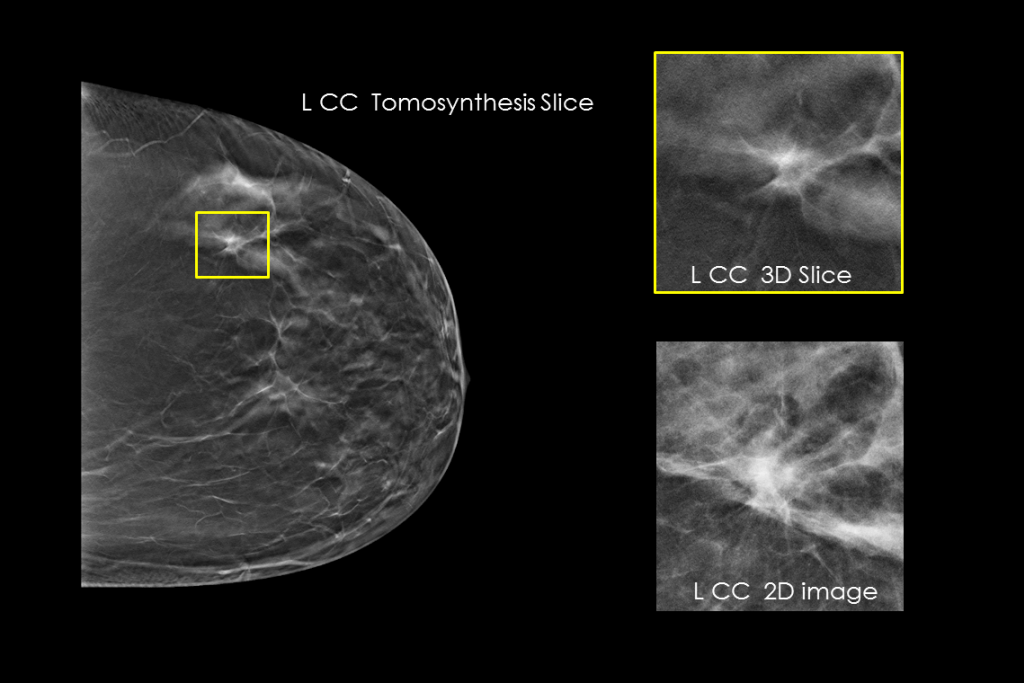

Clinical Images